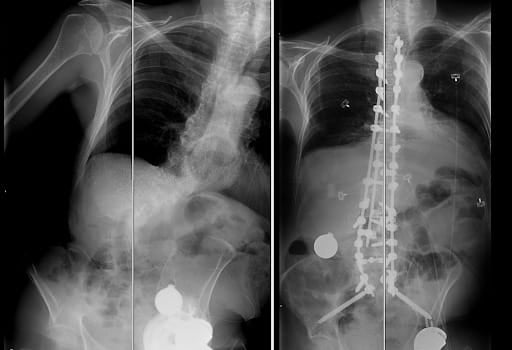

spine surgery before and after x-raysFor Dr. Villar, Michael’s case was a reminder of why he chose to specialize in spine conditions. He expressed how these advanced, complex cases inspire his work and passion to provide dedicated care to his patients.

spine surgery before and after x-raysTo correct Michael’s condition called Kyphoscoliosis, Dr. Villar performed a spinal alignment procedure to help him stand upright. After the surgery, Michael stayed in the hospital for about a week and then spent two more weeks at an inpatient rehab center. By the time he returned home, he was walking again with steady progress each week. “Seeing him return to daily activities has been incredibly meaningful, his whole demeanor has changed. He cannot stop smiling!” said Dr. Villar.